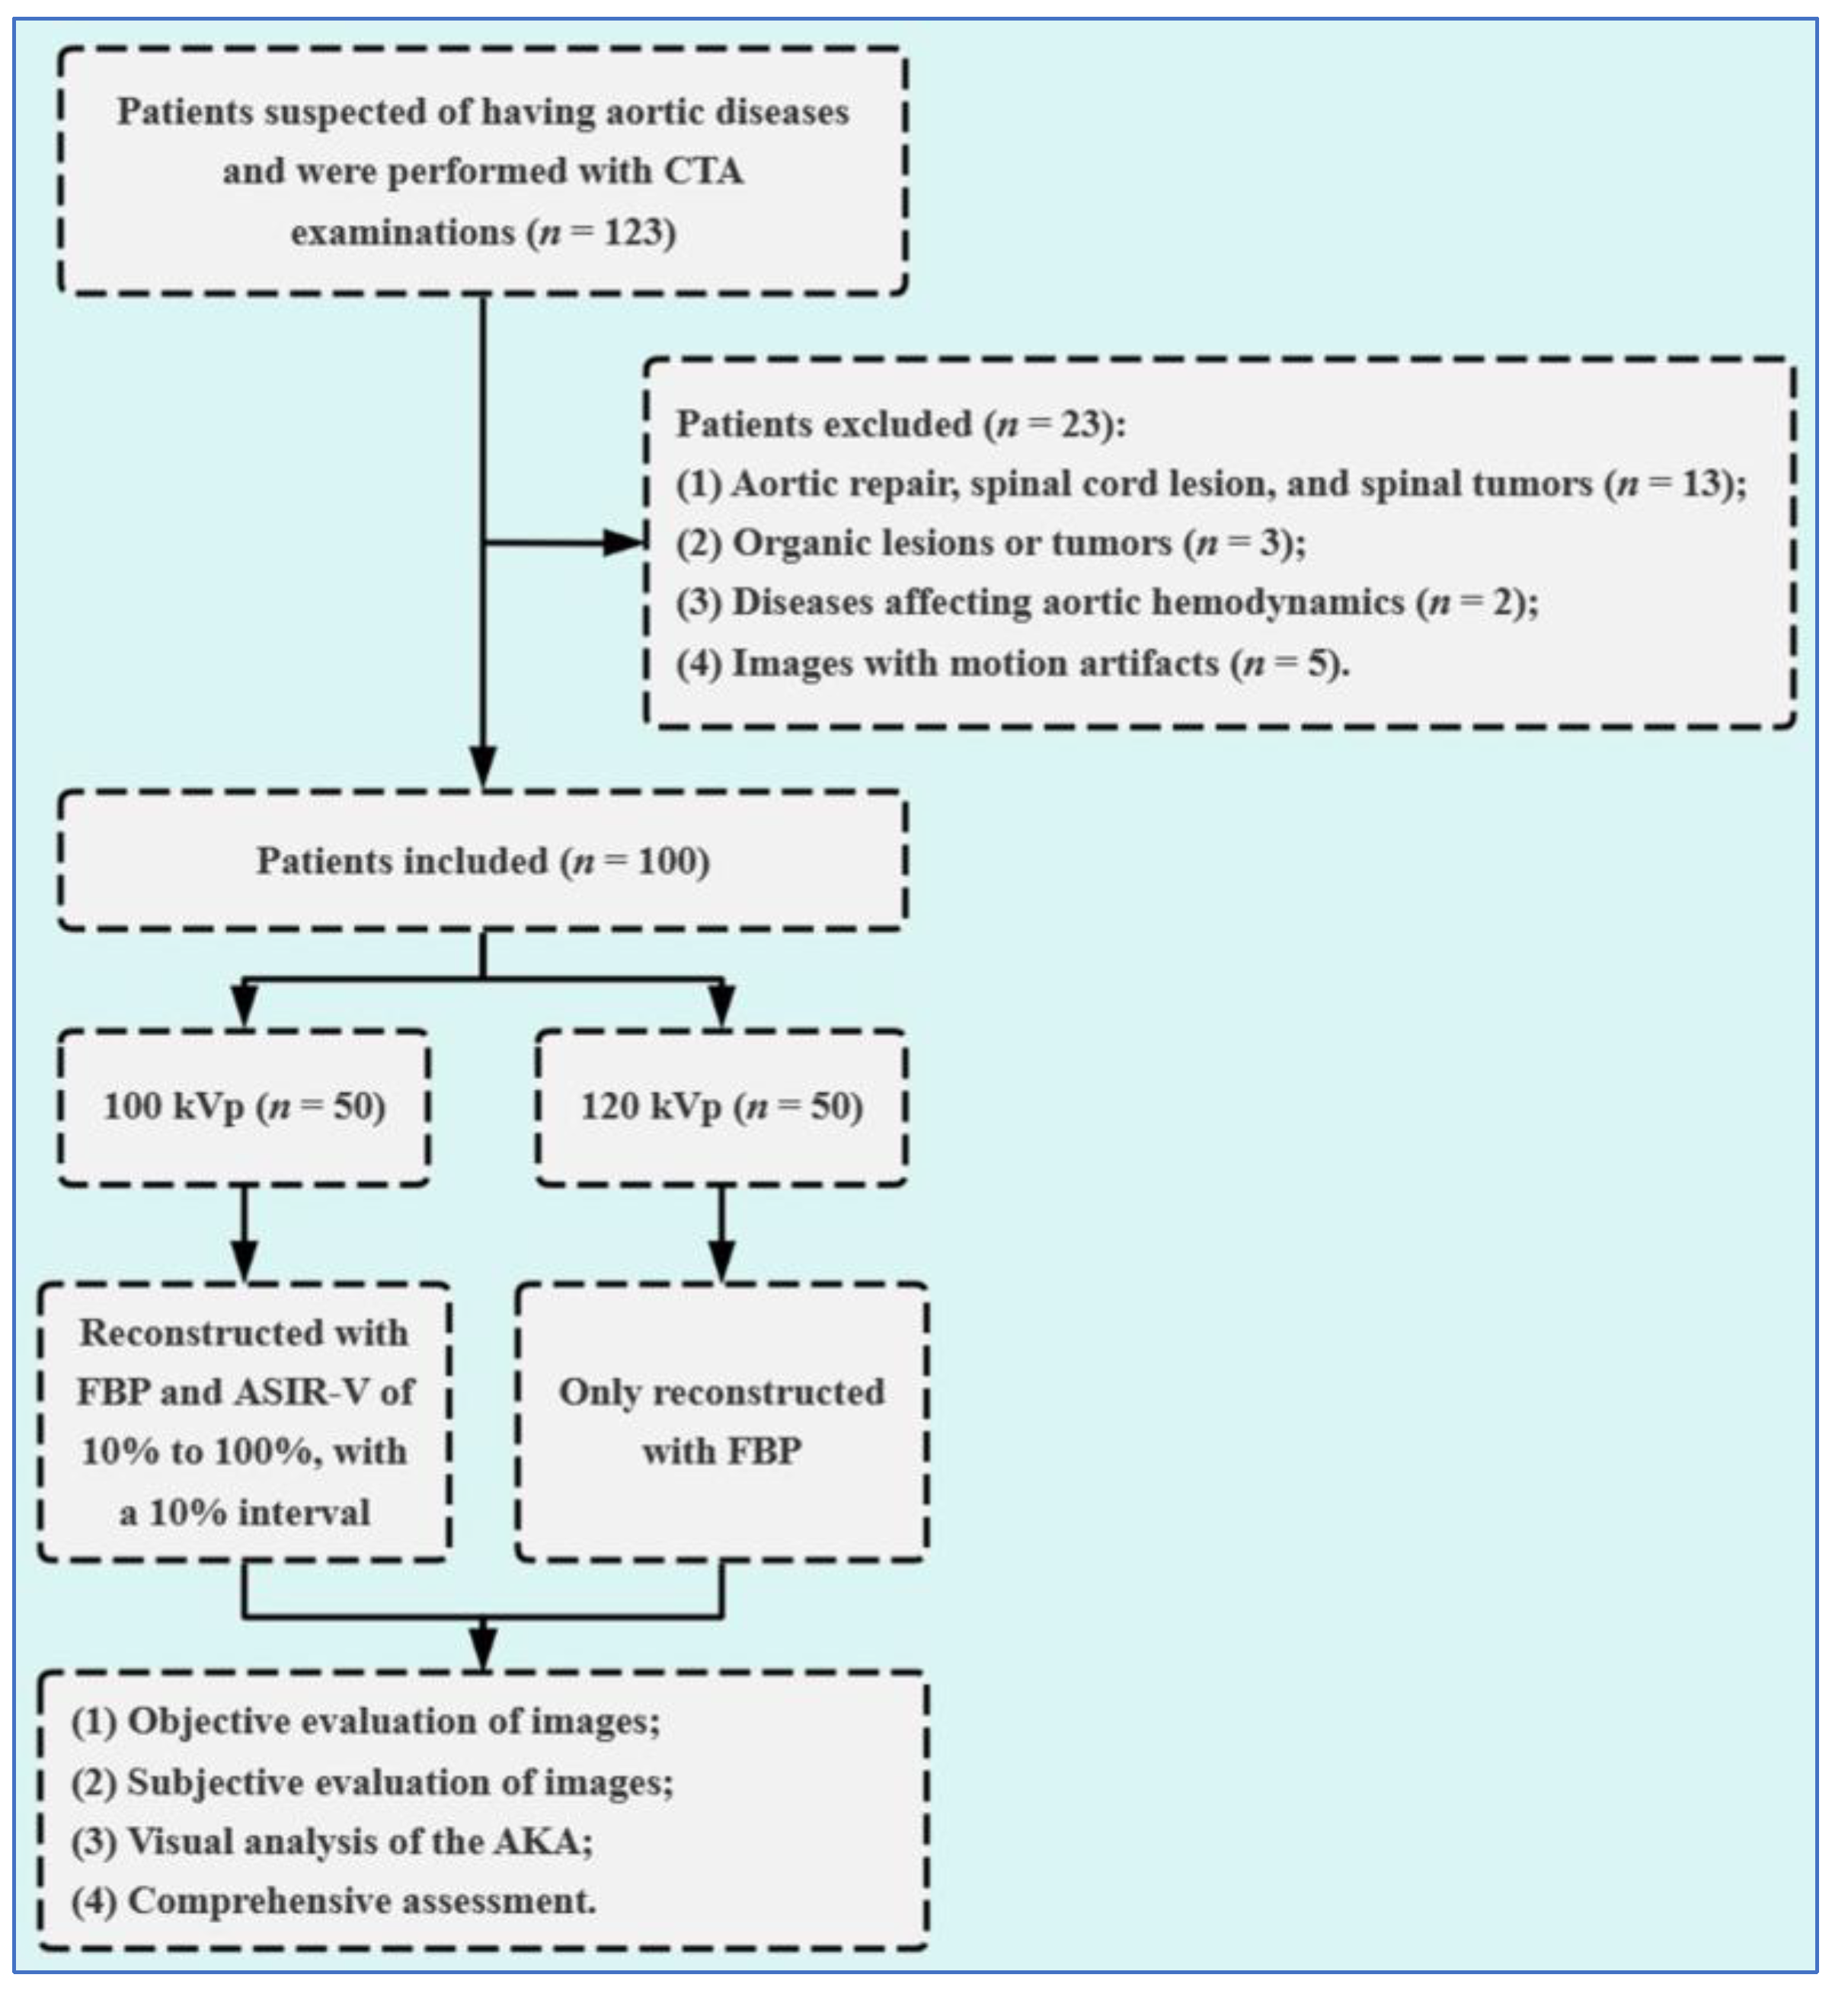

2. Materials and Methods

2.1. Study Population

2.2. Data Acquisition

2.3. Image Reconstruction